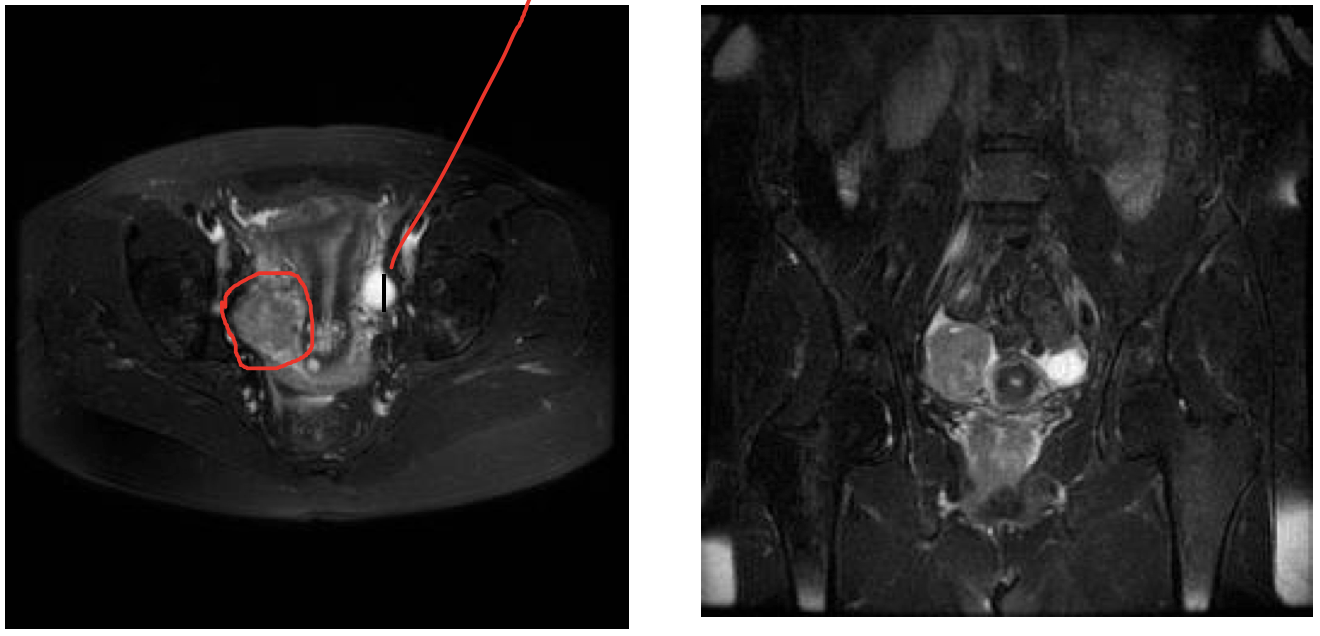

What is circled? What is the line pointing at?

Circled- R ovary w/ aggressive tumor

Line - Normal L ovary